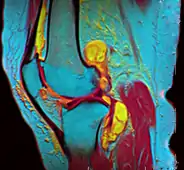

In addition, variants of false color such as pseudocolor, density slicing, and choropleths are used for information visualization of either data gathered by a single grayscale channel or data not depicting parts of the electromagnetic spectrum (e.g. elevation in relief maps or tissue types in magnetic resonance imaging).

A pseudocolor image (sometimes styled pseudo-color or pseudo color) is derived from a grayscale image by mapping each intensity value to a color according to a table or function.[11] Pseudo color is typically used when a single channel of data is available (e.g. temperature, elevation, soil composition, tissue type, and so on), in contrast to false color which is commonly used to display three channels of data.[4]

Depending on the table or function used and the choice of data sources, pseudocoloring may increase the information contents of the original image, for example adding geographic information, combining information obtained from infrared or ultra-violet light, or other sources like MRI scans.[13]